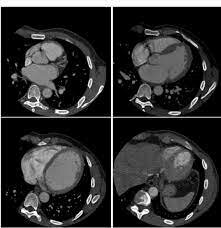

Aparecieron la tomografía de segunda generación y el número de detectores aumentó a 30 y el tiempo de adquisición de datos necesarios a 20 segundos y se sacó para estudiar tórax y abdomen

Mejoraron las imágenes, el tiempo de exploración de 1-6 segundos

Los detectores aumentaron de 400 a 2400 formando un anillo inmóvil y el tubo girando alrededor del objeto 360 grados.